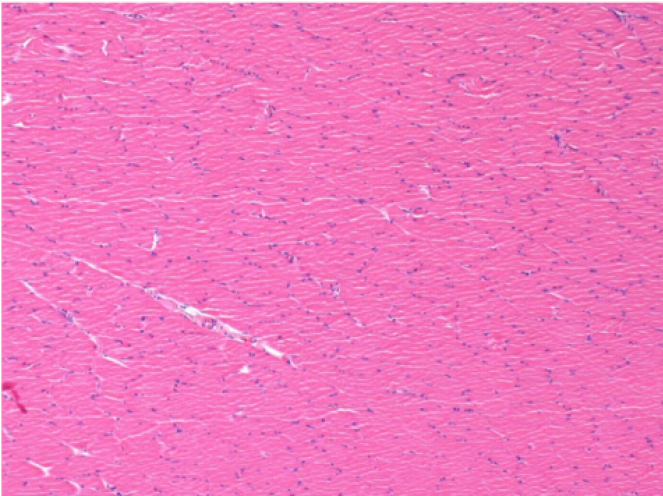

L:Pretibial-No treatment

L :Control 50xD210